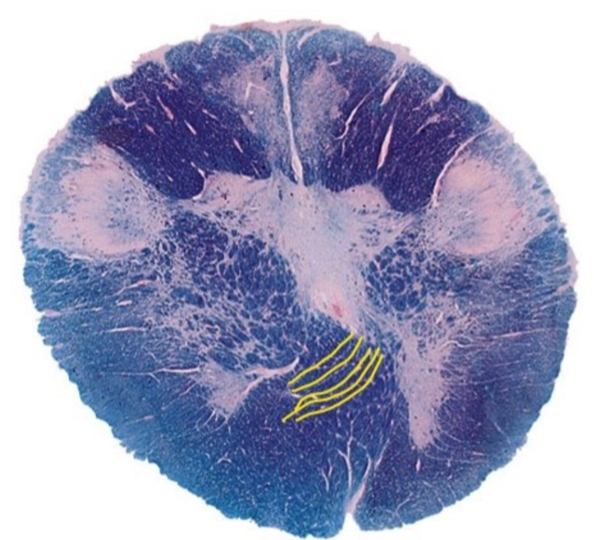

This section is through the ___________________

A

caudal medulla

The yellow line represents?

axons of CN VII

Q

The yellow lines represent?

pyramidal decussation